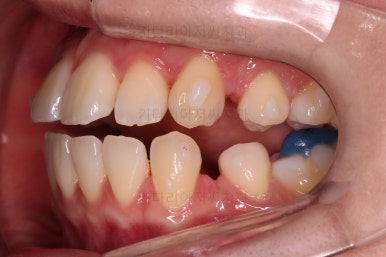

마찬가지로 초진 시 입안의 모습인데요.

전반적으로 약간 삐뚤지만 특히 윗니 앞니가 삐뚤고요.

송곳니는 덧니처럼 튀어나와 보이네요.

그리고 전반적으로 치아가 앞쪽으로 경사되어 있어서 앞니는 뻗친 느낌이 있네요.

가지런하게 하면서 앞니를 뒤로 당겨줘야 여러 가지 문제점들이 개선되기 때문에 발치교정을 했어요.